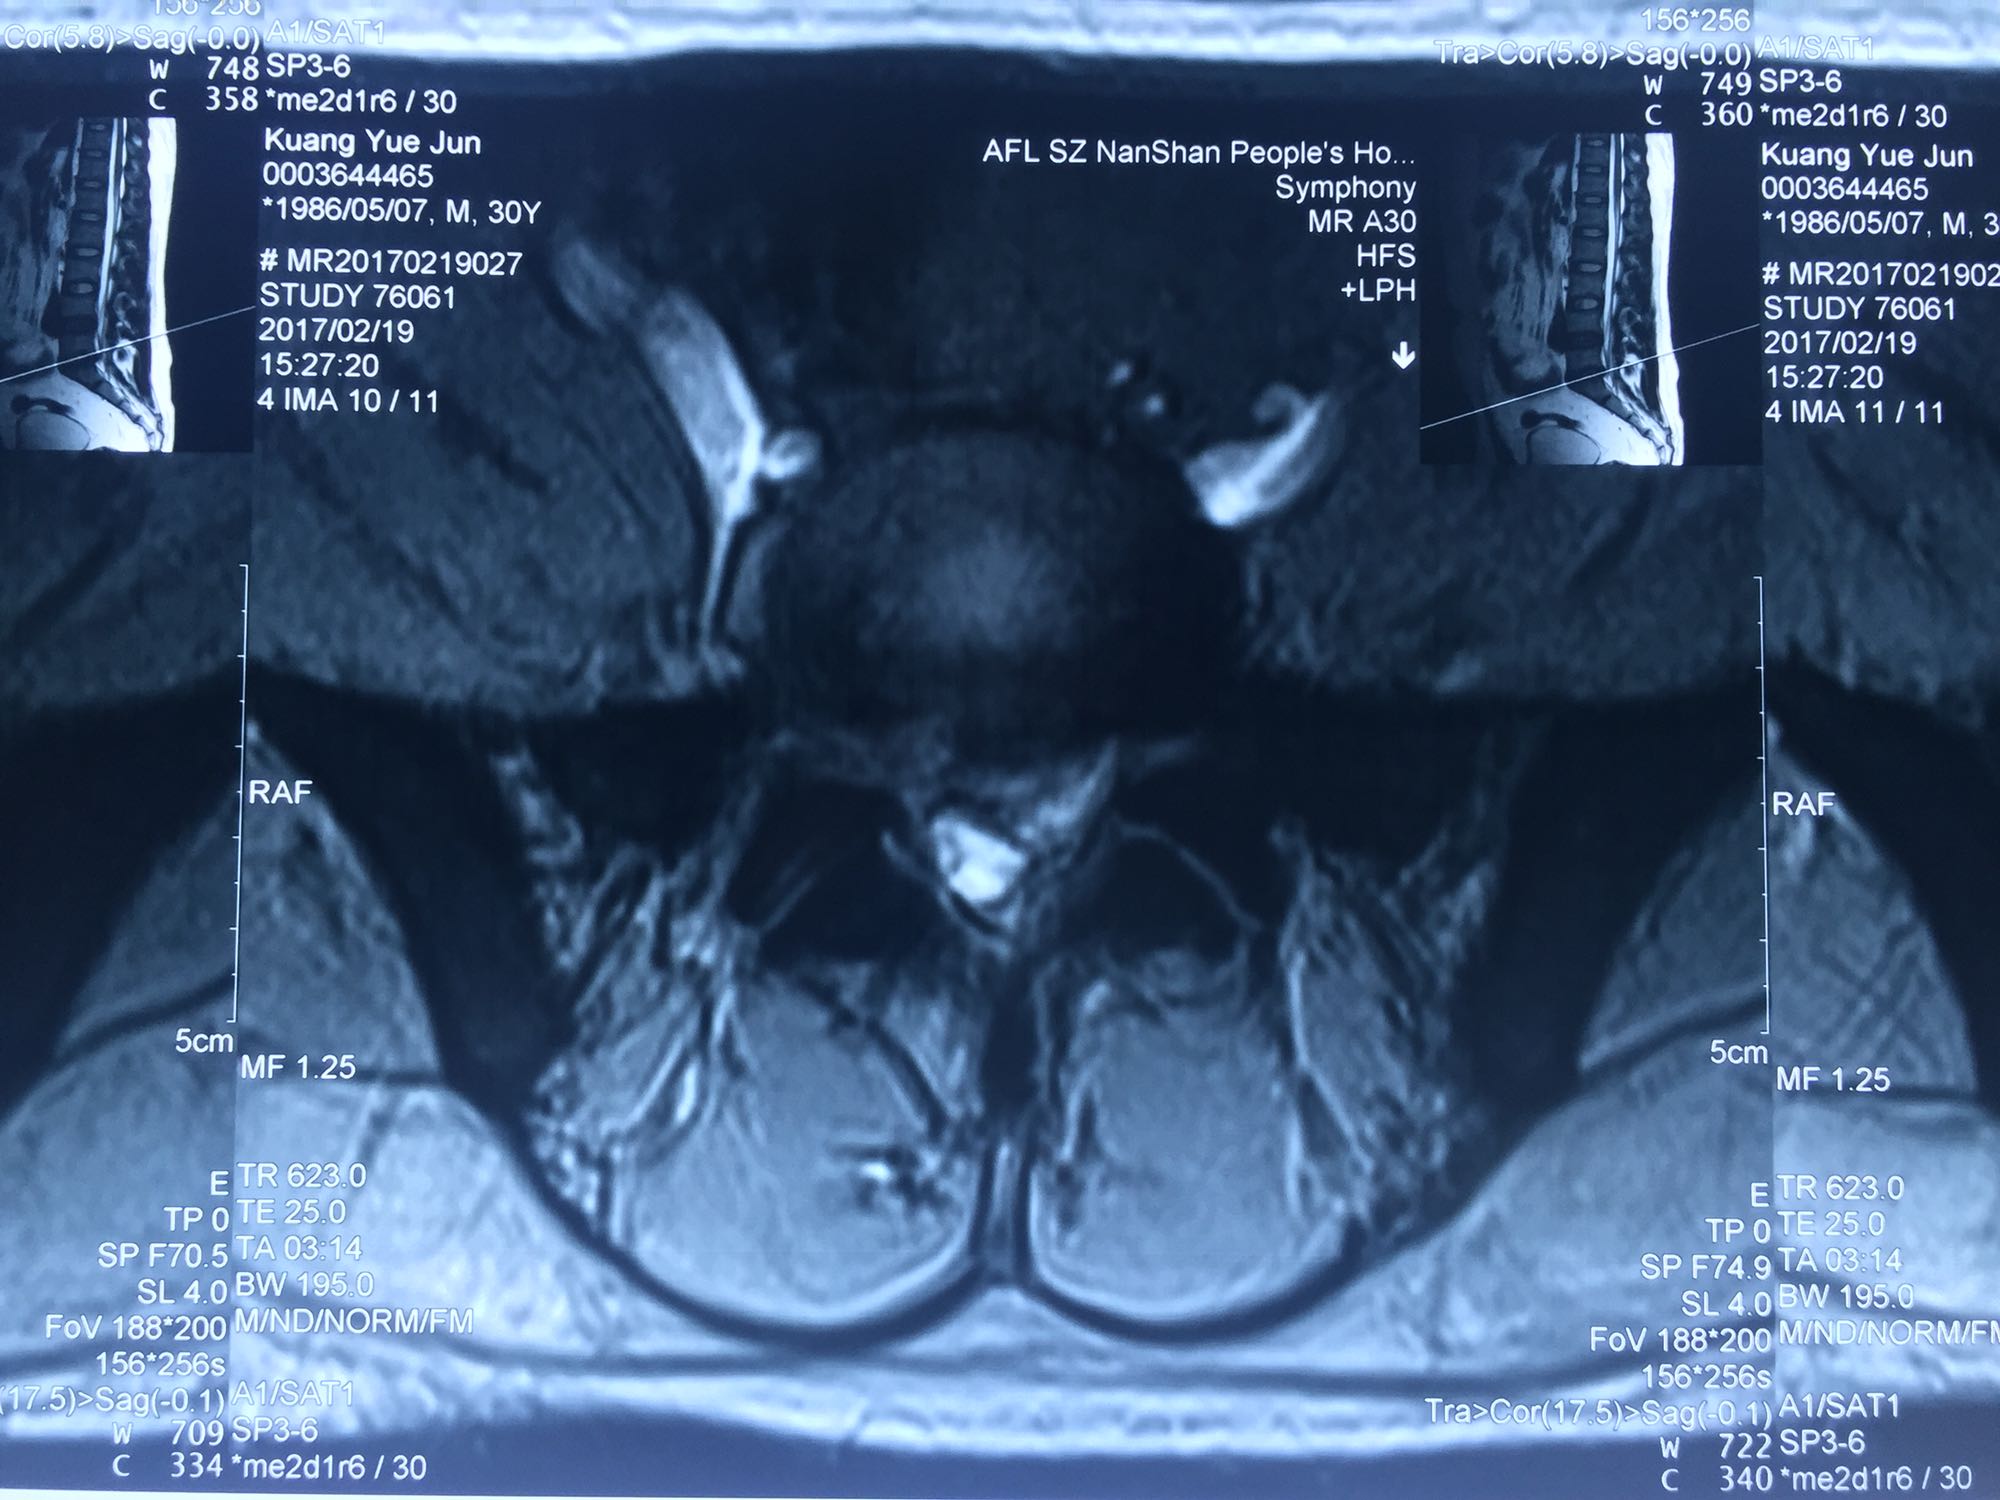

腰骶部肌紧张,腰5骶1棘间及左侧椎旁有压痛及放散痛,左侧坐骨神经出孔处有压痛及放散痛,左侧足背外侧及足底部皮肤感觉麻木,左侧直腿抬高试验阳性(30度)。

诊断:腰5骶1椎间盘突出症 治疗方案:椎间孔镜下经椎板间入路髓核摘除术